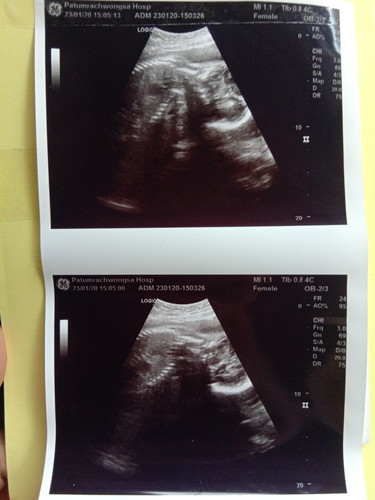

แม่ๆช่วยดูหน่อยว่าหญิงหรือชาย

ตอนนี้ท้อง28+3แล้วจ้า

ภาพไม่บอกเพศจ้า ต้องเป็นมุมหว่างขาค่ะ ถึงจะบอกได้